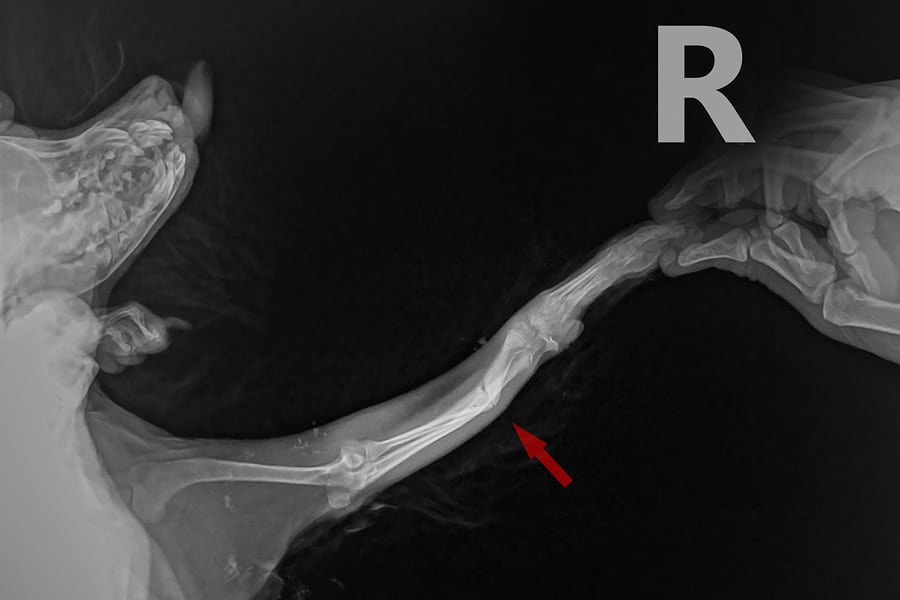

Рентгеновские снимки анатомии собак: строение и здоровье